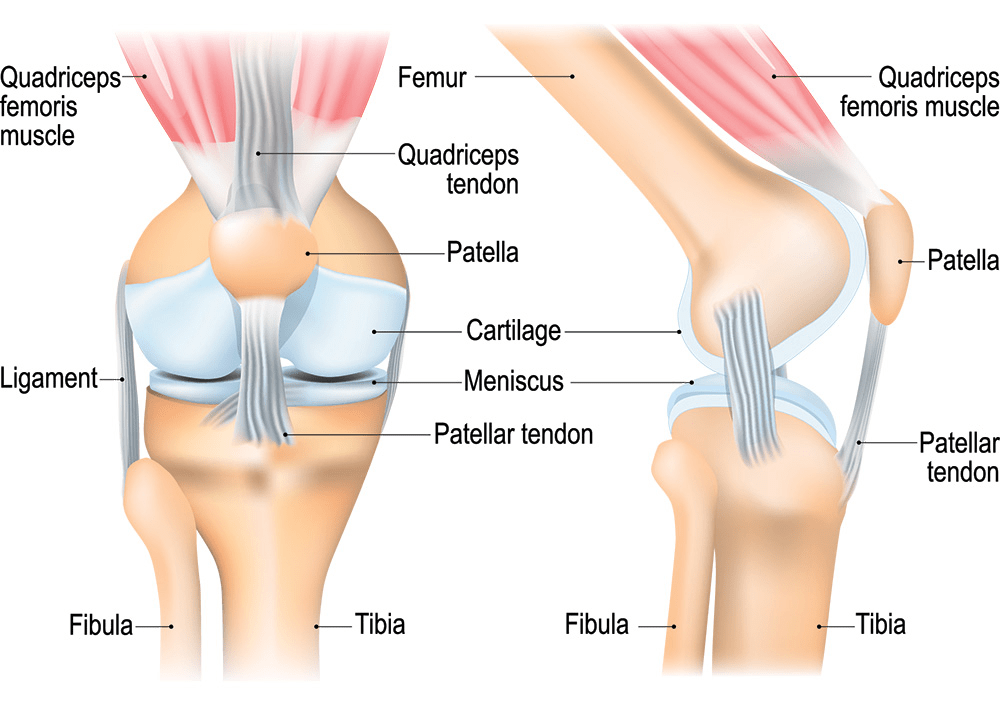

Knees bear your body’s weight daily, with cartilage cushioning bones and ligaments stabilizing joints. Aging, inactivity, or excess strain can wear them down, per the American Academy of Orthopaedic Surgeons. Imagine losing hikes with friends because stiffness wins. Up to 25% of older adults face cartilage loss, raising arthritis risks. Curious how to fight back? These nine methods, inspired by Cleveland Clinic insights, offer practical relief. But first, meet someone who turned their pain around.